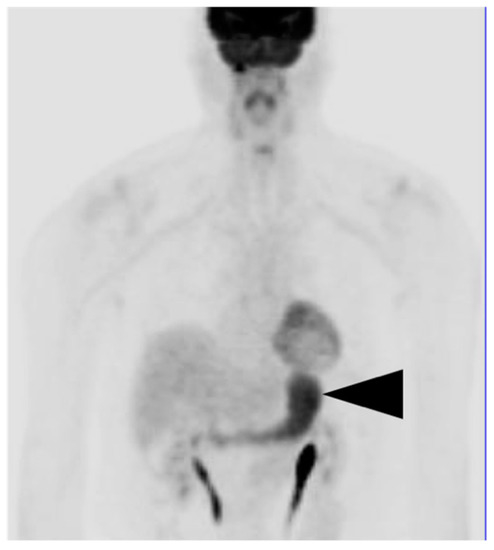

4. Hepatocellular Carcinoma